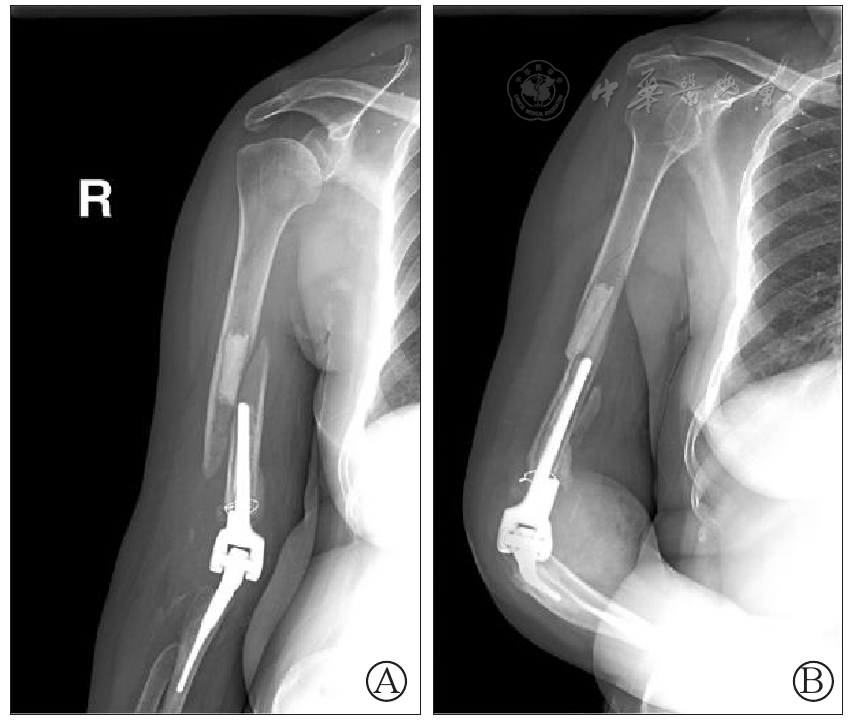

图4 右肘关节正(图A)侧(图B)位片:右侧肘关节置换术后,右侧肱骨下端骨折,断端明显分离移位,关节周围软组织内可见游离骨片影,软组织肿胀

图5 右肘关节假体周围骨折术后正(图A)、侧(图B)位片:右肱骨骨折断端对位对线尚可,内固定稳定,周围软组织内可见小游离骨折碎片,右侧人工肘关节位置良好